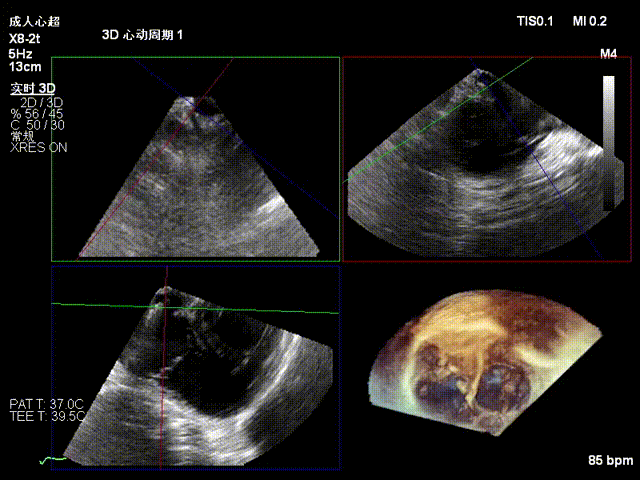

One 14T K-Clip® was implanted at the junction of the posterior and septal annuli of the patient's tricuspid valve, and one 16T K-Clip® was implanted at the junction of the posterior and anterior annuli. The overall annular area was reduced by 45%. Leaflet coaptation was improved, and regurgitation was effectively reduced from severe preoperative to moderate. The overall surgical outcome exceeded expectations, and the procedure was successfully completed.

Preoperative annulus area: 20.6 cm²

After implantation of two clips, the annulus area is 11.8 cm²

Postoperative regurgitation